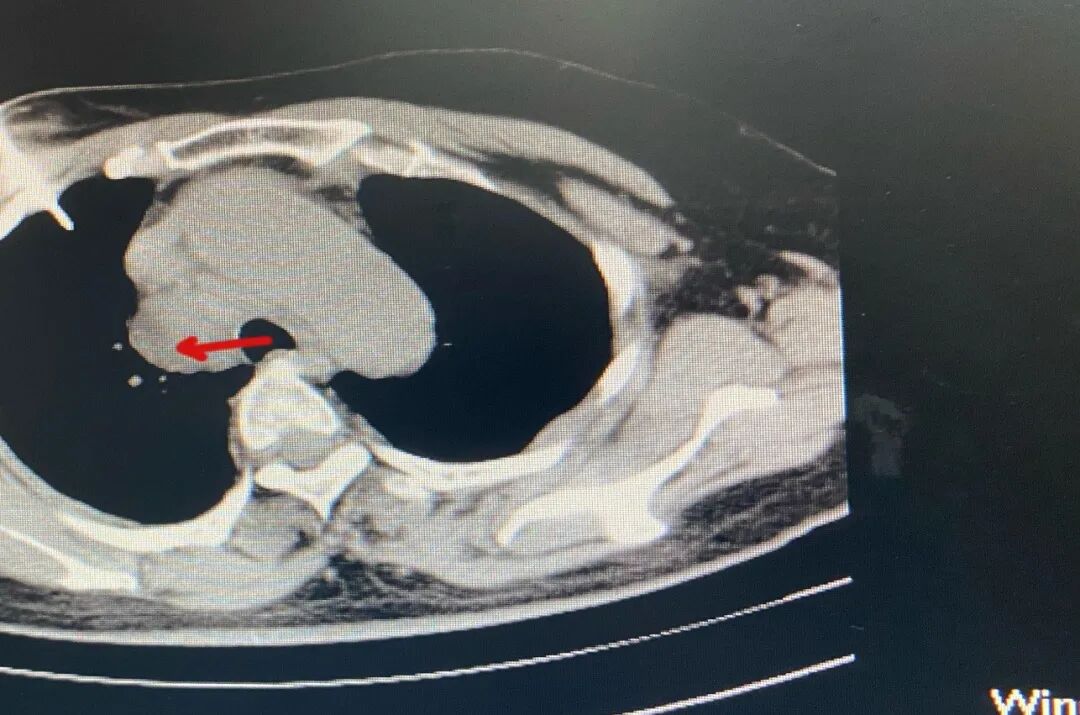

王阿姨的胸悶氣喘的原因是因?yàn)槠?strong style="box-sizing: border-box;">心臟正后方長了一個(gè)占位性腫塊。

▲王阿姨的CT圖

為了明確王阿姨腫塊是良性病變還是惡性病變,必須對腫塊進(jìn)行穿刺活檢,然而阿姨的腫塊的位置“絕佳”,腫塊是位于心臟、肺之間的右中縱膈部位,左邊比鄰上腔靜脈和主動(dòng)脈,右邊是相當(dāng)密集的肺部小血管,這位置可是號稱“死亡穿刺區(qū)”,穿刺問題非常棘手,和家人商議后決定,先使用風(fēng)險(xiǎn)度較少的纖支鏡氣管鏡下活檢初嘗試。